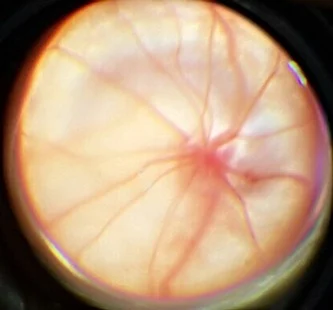

Офтальмоскопия и интегральная полуколичественная оценка состояния глазного дна